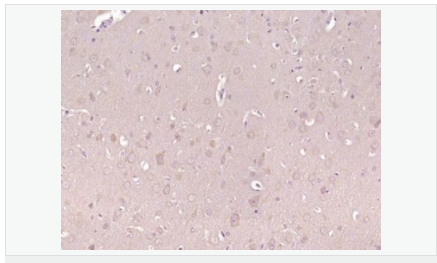

交叉反應(yīng):Human,Mouse,Rat(predicted:Dog,Rabbit) 推薦應(yīng)用:IHC-P,IHC-F,IF,ELISA

| 產(chǎn)品應(yīng)用 | ELISA=1:5000-10000 IHC-P=1:100-500 IHC-F=1:100-500 IF=1:100-500 (石蠟切片需做抗原修復(fù)) not yet tested in other applications. optimal dilutions/concentrations should be determined by the end user. |